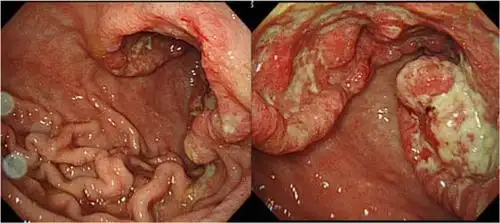

肿瘤外科成功开展新辅助化疗后全腹腔镜下胃癌根治术